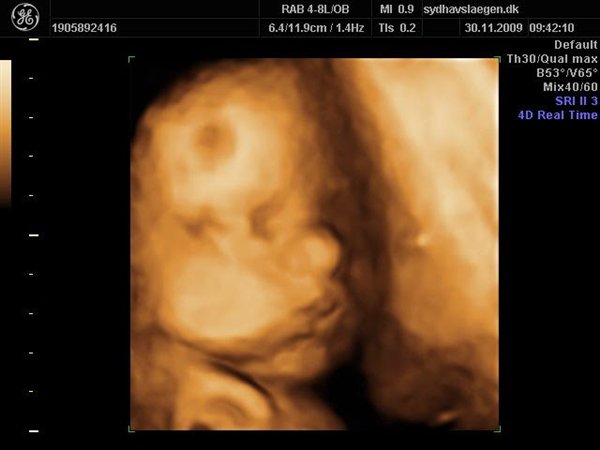

Da jeg snakkede med hende i dag sagde hun at fra uge 27 til og med uge 31 var det bedste tidspunkt at få det gjort....

Vi skal give 1400 kr for 45 minutters total gennem scanning, hvor hun fortæller, undersøger babyen fra top til tå, laver vægtskøn også får vi billeder og dvd med hjem.... Og ja det er da mange penge, men min forlovede har haft en masse vikar timer den her mdr, også sagde han at han syntes vi skulle bruge de penge på noget vi normalt ikke ville have gjort. Han sagde egentlig at jeg kunne gå ud og shoppe for dem, men jeg har termin om ti uger, så gider ærlig talt ikke bruge penge på nyt graviditets tøj, så hellere det her som vi egentlig havde valgt fra pga prisen, men som vi begge to rigtig gerne vil....